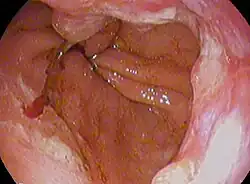

| Endoscopic image of an esophageal adenocarcinoma | |

Although an occlusive tumor may be suspected on a barium swallow or barium meal, the diagnosis is best made with an examination using an endoscope. This involves the passing of a flexible tube with a light and camera down the esophagus and examining the wall, and is called an esophagogastroduodenoscopy. Biopsies taken of suspicious lesions are then examined histologically for signs of malignancy.